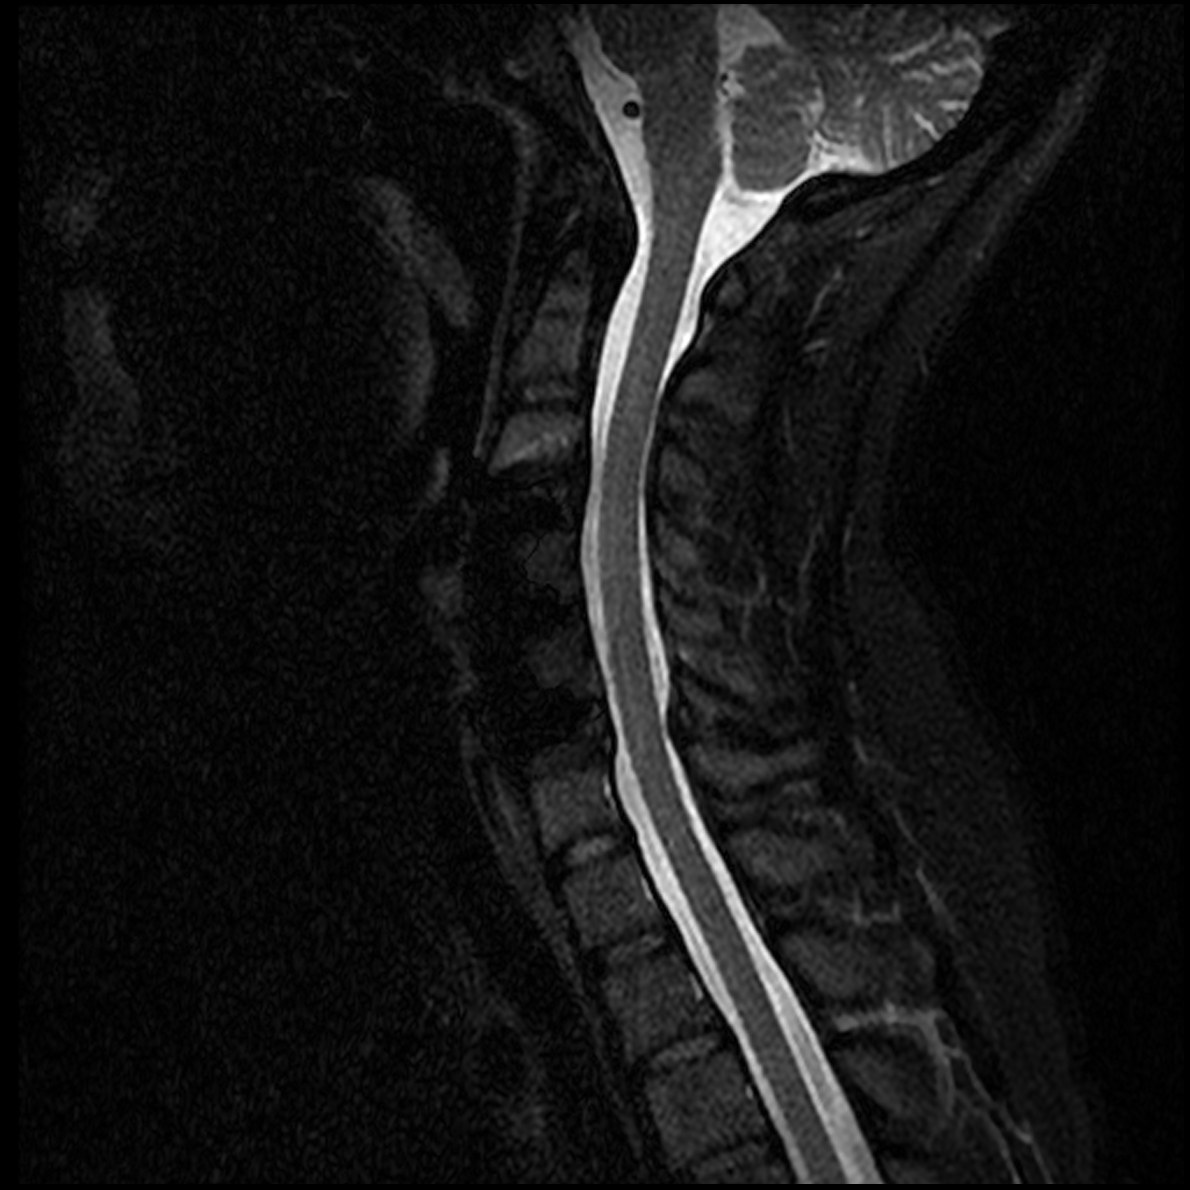

March 2019 MRI

IMPRESSION:

- Complete rupture proximal third anterior cruciate ligament with pivot shift

pattern of bone injuries lateral compartment and contrecoup bone contusion

medial tibial plateau. Joint hemarthrosis. - Complex tear lateral meniscus with inferiorly flipped flap tear extending

into the popliteal hiatus. - Complex tear medial meniscus with outwardly extruded tears of the posterior

horn and body. - Low-grade sprains medial collateral ligament and medial posterior oblique

ligament. - Low-grade sprains fibular collateral ligament and anterolateral ligament.

Intermediate to high-grade sprain popliteofibular ligament and arcuate ligament. - Grade 1 strains vastus lateralis, short head biceps, sartorius, soleus,

popliteus and anterior compartment muscles.